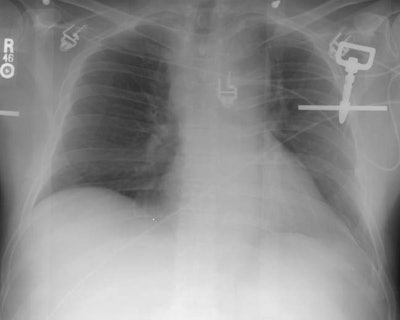

The frontal chest radiograph below was performed on a patient who presented to the emergency department following a 30 foot fall. The radiograph demonstrates widening of the mediastinum and an aortic contour abnormality with loss of the sharp outline of the aortic knob. Many of the other findings of aortic injury were not present and a CT of the chest was performed to evaluate for the presence of aortic injury ( Click here to view the CT scan and arteriogram).